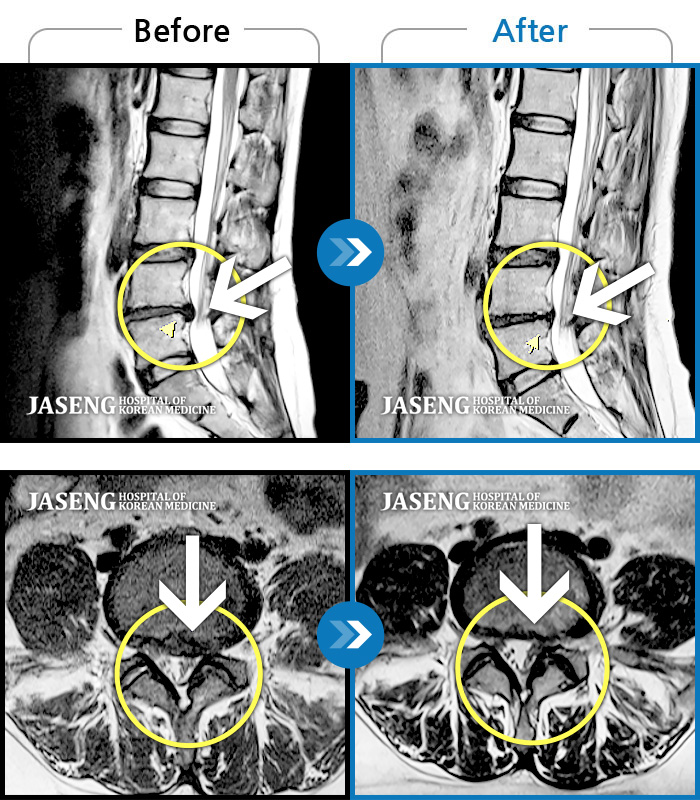

MRI 치료사례

양측 허리 통증, 좌측 하지 후면 통증 및 저림 증상